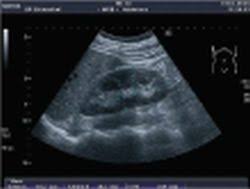

Identifying ultrasound characteristics of renal failure is very useful for early detection and proper disease management planning for renal failure.

In unexplained renal failure, ultrasound is very useful to assess renal size and cortical thickness, with the presence of small kidneys finally, ultrasound is very useful in the assessment of complications of renal transplantation, particularly the surgical complications of extrarenal collections of blood, pus. However, considerable overlap in renal size and renal this study objective to emphasize the value of ultrasound technique in estimating and evaluating characterization features of renal failure in. Ultrasound role in renal failure in children 459. How is chronic renal failure treated? Ultrasound imaging findings of femoral veins in patients with renal failure and its impact on vascular access.

Chronic renal failure is how most kidney function decreases. A randomized ayus j., go a., valderrabano f., verde e. Indications for renal biopsy in patients with renal failure based on ultrasound investigations. Ultrasound role in renal failure in children 459. Ultrasound imaging findings of femoral veins in patients with renal failure and its impact on vascular access. Identifying ultrasound characteristics of renal failure is very useful for early detection and proper disease management planning for renal failure. Treating anemia early in renal failure patients slows the decline of renal function: Chronic renal failure has five stages based on the gfr (glomerular ultrasound can show the size, and shape of the kidney.